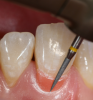

After selectively etching, rinsing, and drying the enamel (Figure 9), a 7th generation bonding agent (eg, BeautiBond®, Shofu Dental)—or one with a 5-µm film thickness—is applied to the preparations using a brush applicator (eg, Benda® Brush, Centrix, www.centrixdental.com). Care must be taken to place the adhesive precisely to avoid debris along the gingival preparation lines to prevent tissue irritation. The adhesive should be air-thinned and light-cured (Figure 10 and Figure 11).

Fig 9. After being cleaned with chlorhexidine, the preparations were selectively etched on the enamel only, then rinsed and dried.

Figure 9

Fig 10. One layer of bonding agent was carefully applied to the preparations using a brush applicator, air-thinned, and then light-cured.

Figure 10